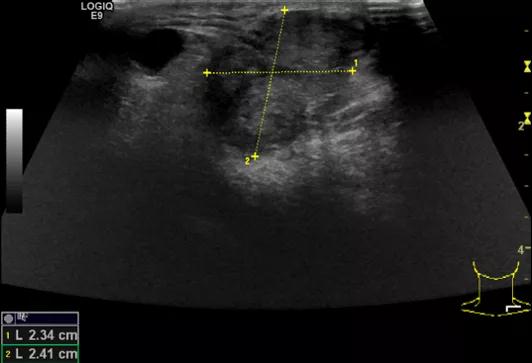

第5例是乳腺癌的患者,右乳恶性肿瘤术后化疗后1年出现淋巴结转移,患者基本情况差,拒绝放化疗,行局部热消融后也实现充盈缺损,术后一个月强化信号消失。

(病例5图例)